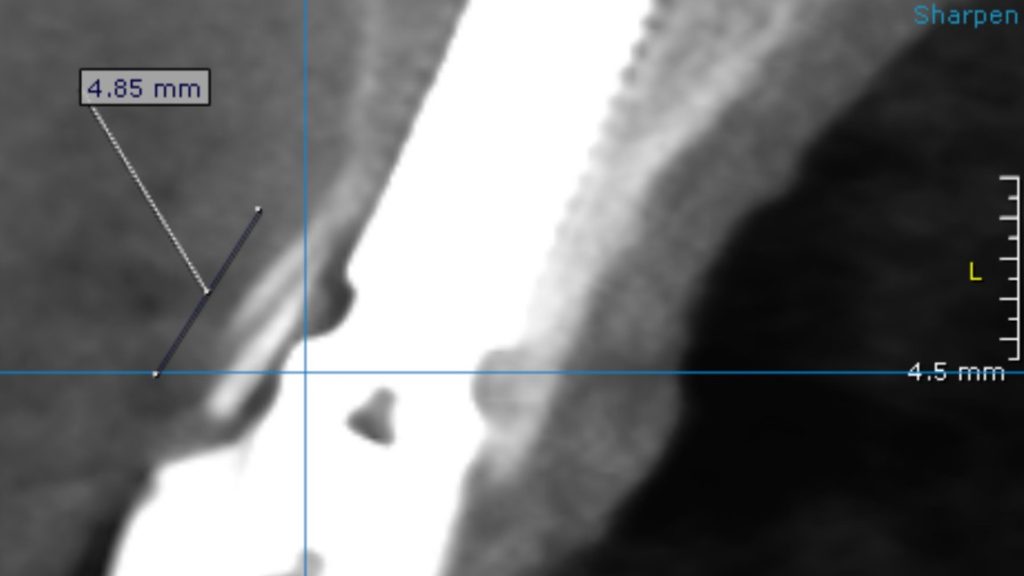

Surgical stage